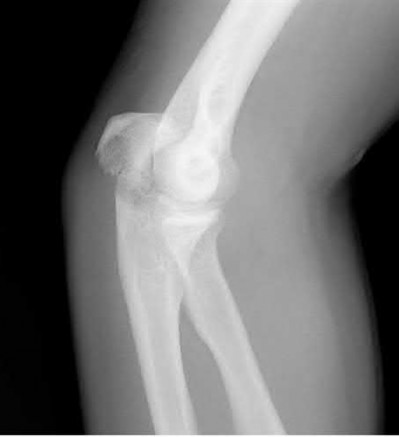

Figures A-C are the radiographs of a 26-year-old male who presents to the emergency department following a motocross accident. Two attempts at a closed reduction by the on-call orthopedic resident were unsuccessful. Figures D and E are the pre-operative axial CT-images that were obtained. The patient undergoes surgical fixation seen in Figure F. Limitations in post-operative dorsiflexion is likely influenced by which of the following?

Figures A-C: The initial radiographs reveal the posterior subluxation of the talus with associated posterior subluxation of the fibula without significant coronal plane deformity. This deformity should raise the suspicion of a Bosworth fracture-dislocation, especially if closed reduction is not successful. Figures D and E: Axial CT images demonstrating Bosworth fracture-dislocation of the fibula entrapped behind the tibia. Also, note the fracture extension to the posteromedial rim in this posterior pilon variant.

Figure F: Positioning of the plate suggests a posterolateral approach to address both the fibula and posterior malleolus fractures.